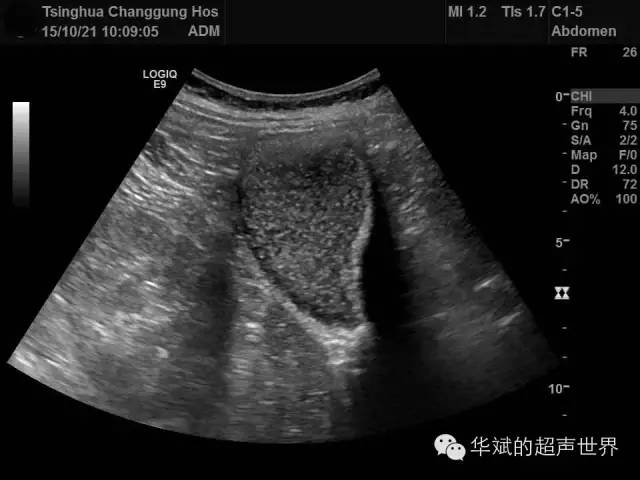

超声可见胆囊内的胆汁淤积(胆泥形成)并可见一层状的高回声伴有显著的声影,与瘀滞的胆汁之间有明显的分界线,改变体位可见该分界线缓慢变化移位。充满性的胆囊钙乳症仅在胆囊区探及声影明显的弧形强回声,此时很难与充满性结石(陶瓷胆囊)相鉴别。

下面的病例为62岁女性,上腹部隐痛就诊。

图1 胆囊钙乳症。胆囊内可见浓缩的胆汁与伴有明显声影的钙乳之间的强回声分界线。